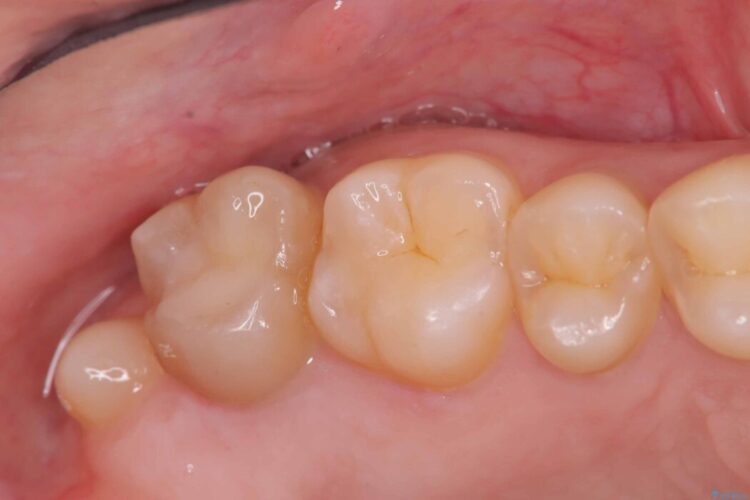

メタルフリー|全ての銀歯をセラミックへ

メタルフリー|全ての銀歯をセラミックへ ビフォー メタルフリー|全ての銀歯をセラミックへ アフター

口腔内の銀歯を全て無くし、白く健康的な状態にしたいとご来院された患者様です。